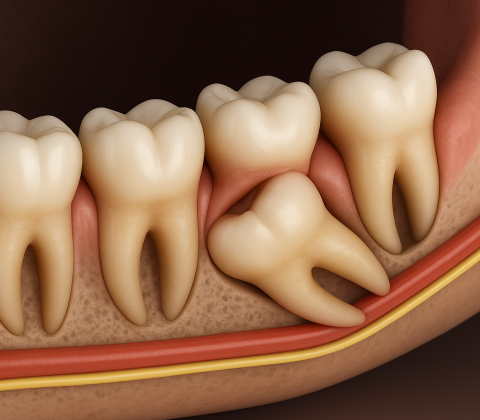

دندان عقل نهفته چیست و چه زمانی باید جراحی شود؟

پاراگراف مقدمهدندان عقل نهفته یکی از مشکلات رایج در دندانپزشکی است که اغلب نیاز به جراحی دارد. اگر این دندانها بهدرستی رشد نکنند یا در

دندان عقل نهفته چیست؟

هنگامی که دندان عقل به درستی از لثه بیرون نیاید، دندانپزشکان از آن به عنوان دندان عقل نهفته یاد میکنند. این میتواند منجر به درد لثه و فک